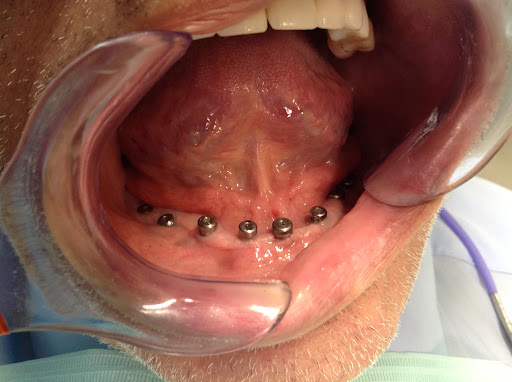

Frank Heravi, DDS, delivers an exceptional dental experience on Long Island, combining state-of-the-art CEREC technology for same-day crowns and veneers with IV sedation for anxiety-free care. The office at 243 Jericho Tpke uses digital impressions and 3-D imaging so patients skip messy molds while achieving precise, custom results in a single visit. Families value caring pediatric treatment, early preventive programs, and orthodontic offerings under one roof, while adults appreciate minimally invasive implants and sleep-apnea solutions. Friendly staff, flexible financing, and a comprehensive warranty reinforce trust, making appointments at (516) 616-4900 or yourlongislanddentist.com both convenient and reassuring.